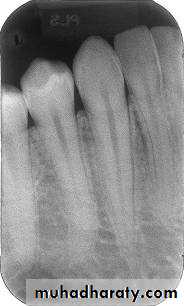

Mandibular premolar region

Mandibular molar region